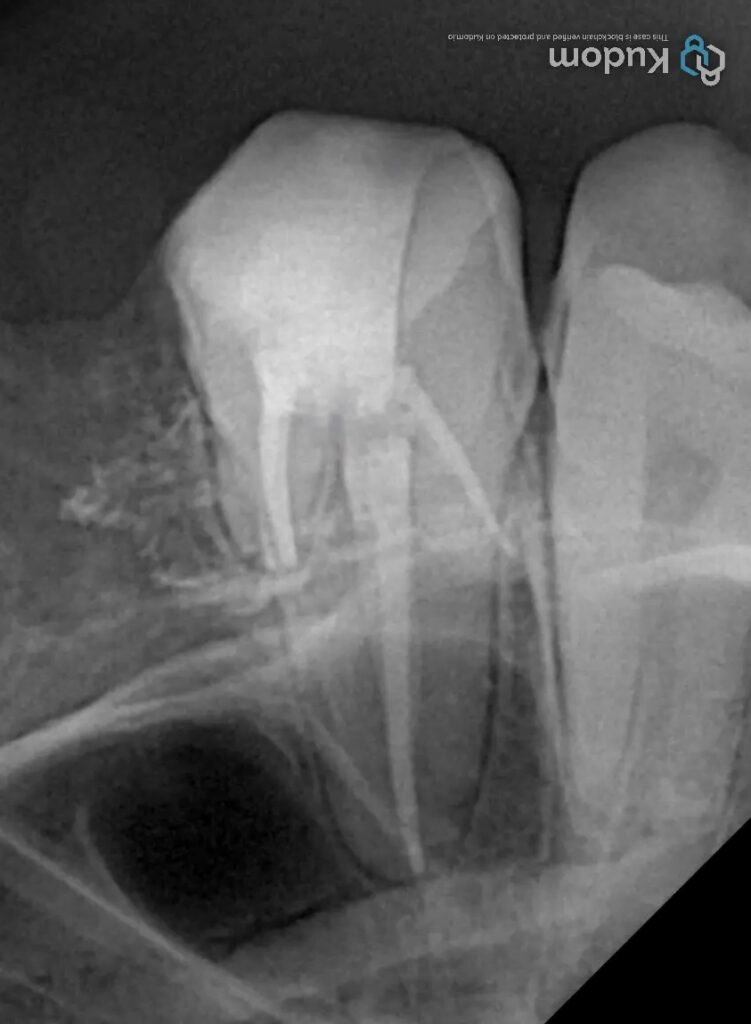

MB2 Canal Identification and Negotiation

The MB2 canal was located along the developmental groove between the MB1 and palatal canals. Key principles applied included:

- Use of high magnification and coaxial illumination

- Ultrasonic troughing with minimal pressure

- Visual confirmation of hemorrhagic points and anatomical cues

Once identified, the MB2 canal was negotiated with small, pre-curved stainless steel hand files, followed by establishment of a reproducible glide path. Working length was confirmed using electronic apex location and radiographic verification.

Obturation and Coronal Seal

Obturation was performed once dryness and apical control were confirmed. Special attention was given to the MB2 canal to ensure three-dimensional sealing. Immediate coronal sealing was carried out to prevent reinfection, forming the foundation for subsequent restorative planning.